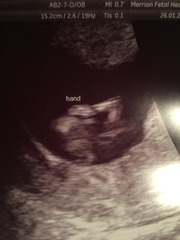

Mslg · 27/01/2016 17:02

Hi ladies, thank you all so much for your words of support. I had them as my mantra when waiting for the scan and all was well. Such a relief!

Due date was pushed forward by two days and is now the 6th August. So surreal seeing the baby somersaulting and wriggling out of the sonographers way. They struggled to get the Nuchal measurements at first and then baby moved. DP, bless him, was shocked. He thought they grew in a stationary mode until a certain gestation 😂